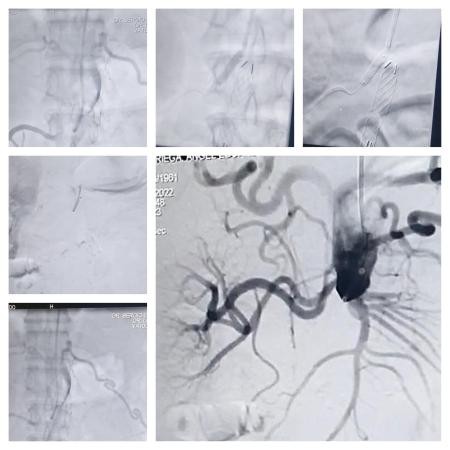

El procedimiento fue realizado por un equipo de profesionales del INCOR conformado por los Dres. Sergio Ludueña, hemodinamista, y Alejandro Flores, cirujano vascular.

Al respecto, el Dr. Sergio Ludueña informó que la intervención fue realizada a un fumador severo de 62 años, que contaba con un importante deterioro, tanto a nivel respiratorio como a nivel vascular, con obstrucciones coronarias en arteras periféricas y epoc.

En ese sentido, el profesional de la salud manifestó: “Tenía síndrome de Leriche, que es lo que tratamos”, y continuó: “Tenía ocluida totalmente la aorta a nivel del nacimiento de la única arteria renal, porque la otra se había tapado”.

“Era un paciente complejo al que hubo que solucionarle primero el problema de las arterias coronarias. Le colocamos 4 (cuatro) stend en las arterias del corazón, y abordamos la recanalización de la arteria aorta”, detalló Ludueña.

Por su parte, el hemodinamista del INCOR precisó: “Este procedimiento se denomina híbrido, ya que se realiza de manera mínimamente invasiva, y trabajamos en equipo junto al cirujano vascular el Dr. Alejandro flores”, y recordó: “Antes se realizaba de una manera muy invasiva. Se realizaba una incisión desde la zona del estómago hasta la base del pubis, y por la complejidad de la salud del paciente, presentaba poca tolerancia a la anestesia general, no era viable”.

El Dr Sergio Ludueña explicó: “Nosotros ingresamos por el brazo hasta la ingle derecha con catéteres y cuerdas. Los elementos van abriendo el paso para dilatar con balones en forma progresiva, y posteriormente se le coloca la endopróteisis para impermeabilizar la aorta. Con esto generamos un eje de flujo hacia la pierna derecha”.

“Una vez que se abre eso, se realiza un bypass que va a cruzar a la otra pierna para lograr una perfusión que permita mejorar la calidad de vida del paciente, mejorando la circulación en sus extremidades, ya que el paciente se encuentra en silla de ruedas”, afirmó el hemodinamista del INCOR.